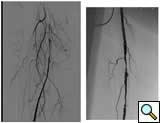

Case 2: A 74-year-old male with new onset severe claudication and threatened toes on the right side. An up-and-over wire was able to be advanced into the superficial femoral artery (but was totally occlusive). Cryoablation restored patency (Figure 2).

![]() |

| Figure 2 |